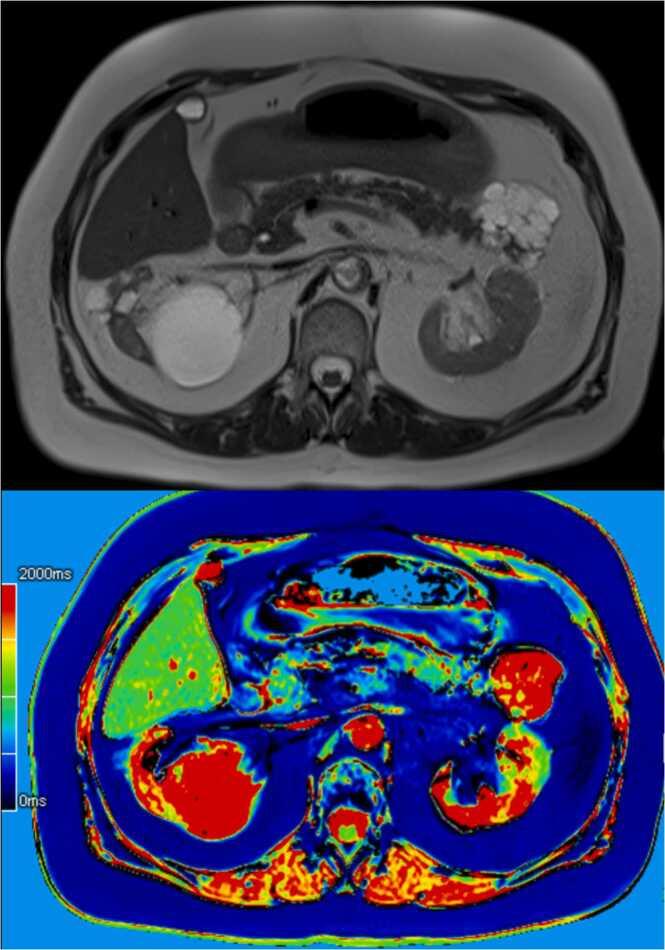

Conventional T1- and T2-weighted magnetic resonance imaging (MRI) of the pancreas can vary significantly due to factors such as scanner differences and pulse sequence variations. This review explores T1 and T2 mapping techniques, modern MRI methods providing quantitative information about tissue relaxation times. Various T1 and T2 mapping pulse sequences are currently under investigation. Clinical and research applications of T1 and T2 mapping in the pancreas include their correlation with fibrosis, inflammation, and neoplasms. In chronic pancreatitis, T1 mapping and extracellular volume (ECV) quantification demonstrate potential as biomarkers, aiding in early diagnosis and classification. T1 mapping also shows promise in evaluating pancreatic exocrine function and detecting glucose metabolism disorders. T2* mapping is valuable in quantifying pancreatic iron, offering insights into conditions like thalassemia major. However, challenges persist, such as the lack of consensus on optimal sequences and normal values for healthy pancreas relaxometry. Large-scale studies are needed for validation, and improvements in mapping sequences are essential for widespread clinical integration. The future holds potential for mixed qualitative and quantitative models, extending the applications of relaxometry techniques to various pancreatic lesions and enhancing routine MRI protocols for pancreatic pathology diagnosis and prognosis.